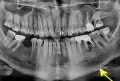

Проблема следующая: болит под коронкой зуб, врач сделал томографию, и по результатам сказал удалять. Записалась на удаление, но все же хотела бы узнать несколько мнений.

Прикладываю скрин томографии, но не рассчитываю, что он информативен. Если все же по нему можно что-то сказать, буду рада услышать Ваше мнение.